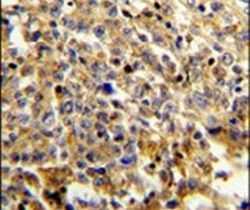

Supportive validation

- Submitted by

- Invitrogen Antibodies (provider)

- Main image

- Experimental details

- Immunohistochemical analysis of formalin-fixed, paraffin-embedded human lymphoma tissue using a NCF4 polyclonal antibody (Product # PA5-14593), followed by HRP-conjugated secondary antibody and DAB staining.